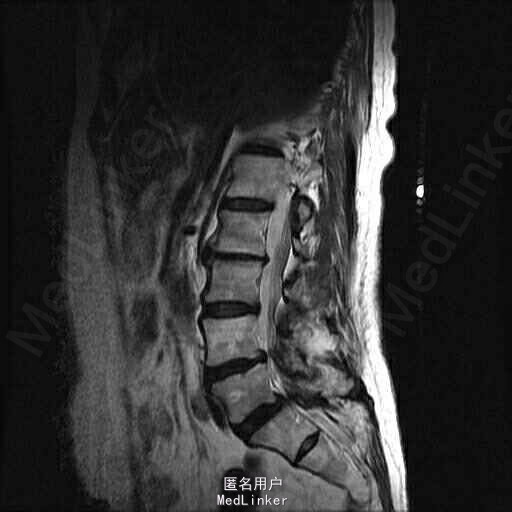

查体:脊柱侧弯,上肢无麻木,疼痛感觉异常,腰部右侧疼痛,右下肢及右臀部疼痛,麻木感。双侧肌力及肌张力可,膝腱反射(+),踝反射(+),病理征(—),直腿抬高试验。右侧40度,左侧55度。 辅助检查:腰椎x线片:腰椎侧弯,腰椎退行性改变,L5椎体略行前滑脱 脊柱全长:胸腰段呈S形,L5椎体向前滑脱,L3椎体略变扁,颈胸腰椎退行性改变 MRI:脊柱侧弯,L2-3,L3-L4,L4-L5,L5-S1椎间盘突出,相应节段椎管狭窄

诊断:腰椎侧弯,腰椎椎管狭窄 治疗:手术矫形:早期侧路减压融合,后期再行后路固定。